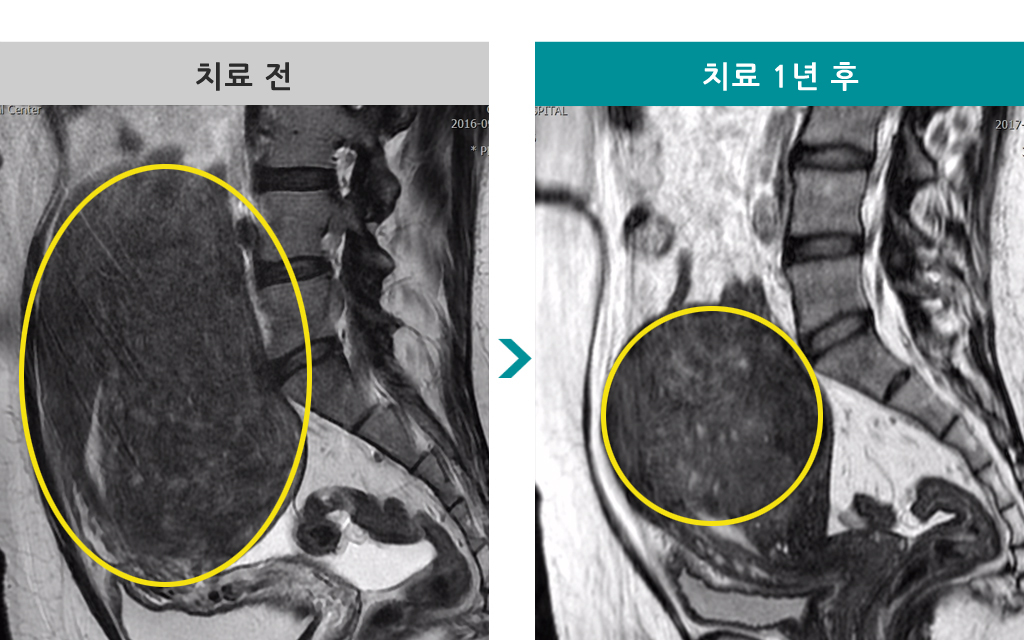

48세 [자궁근종 색전술] 전후 MRI사진 비교